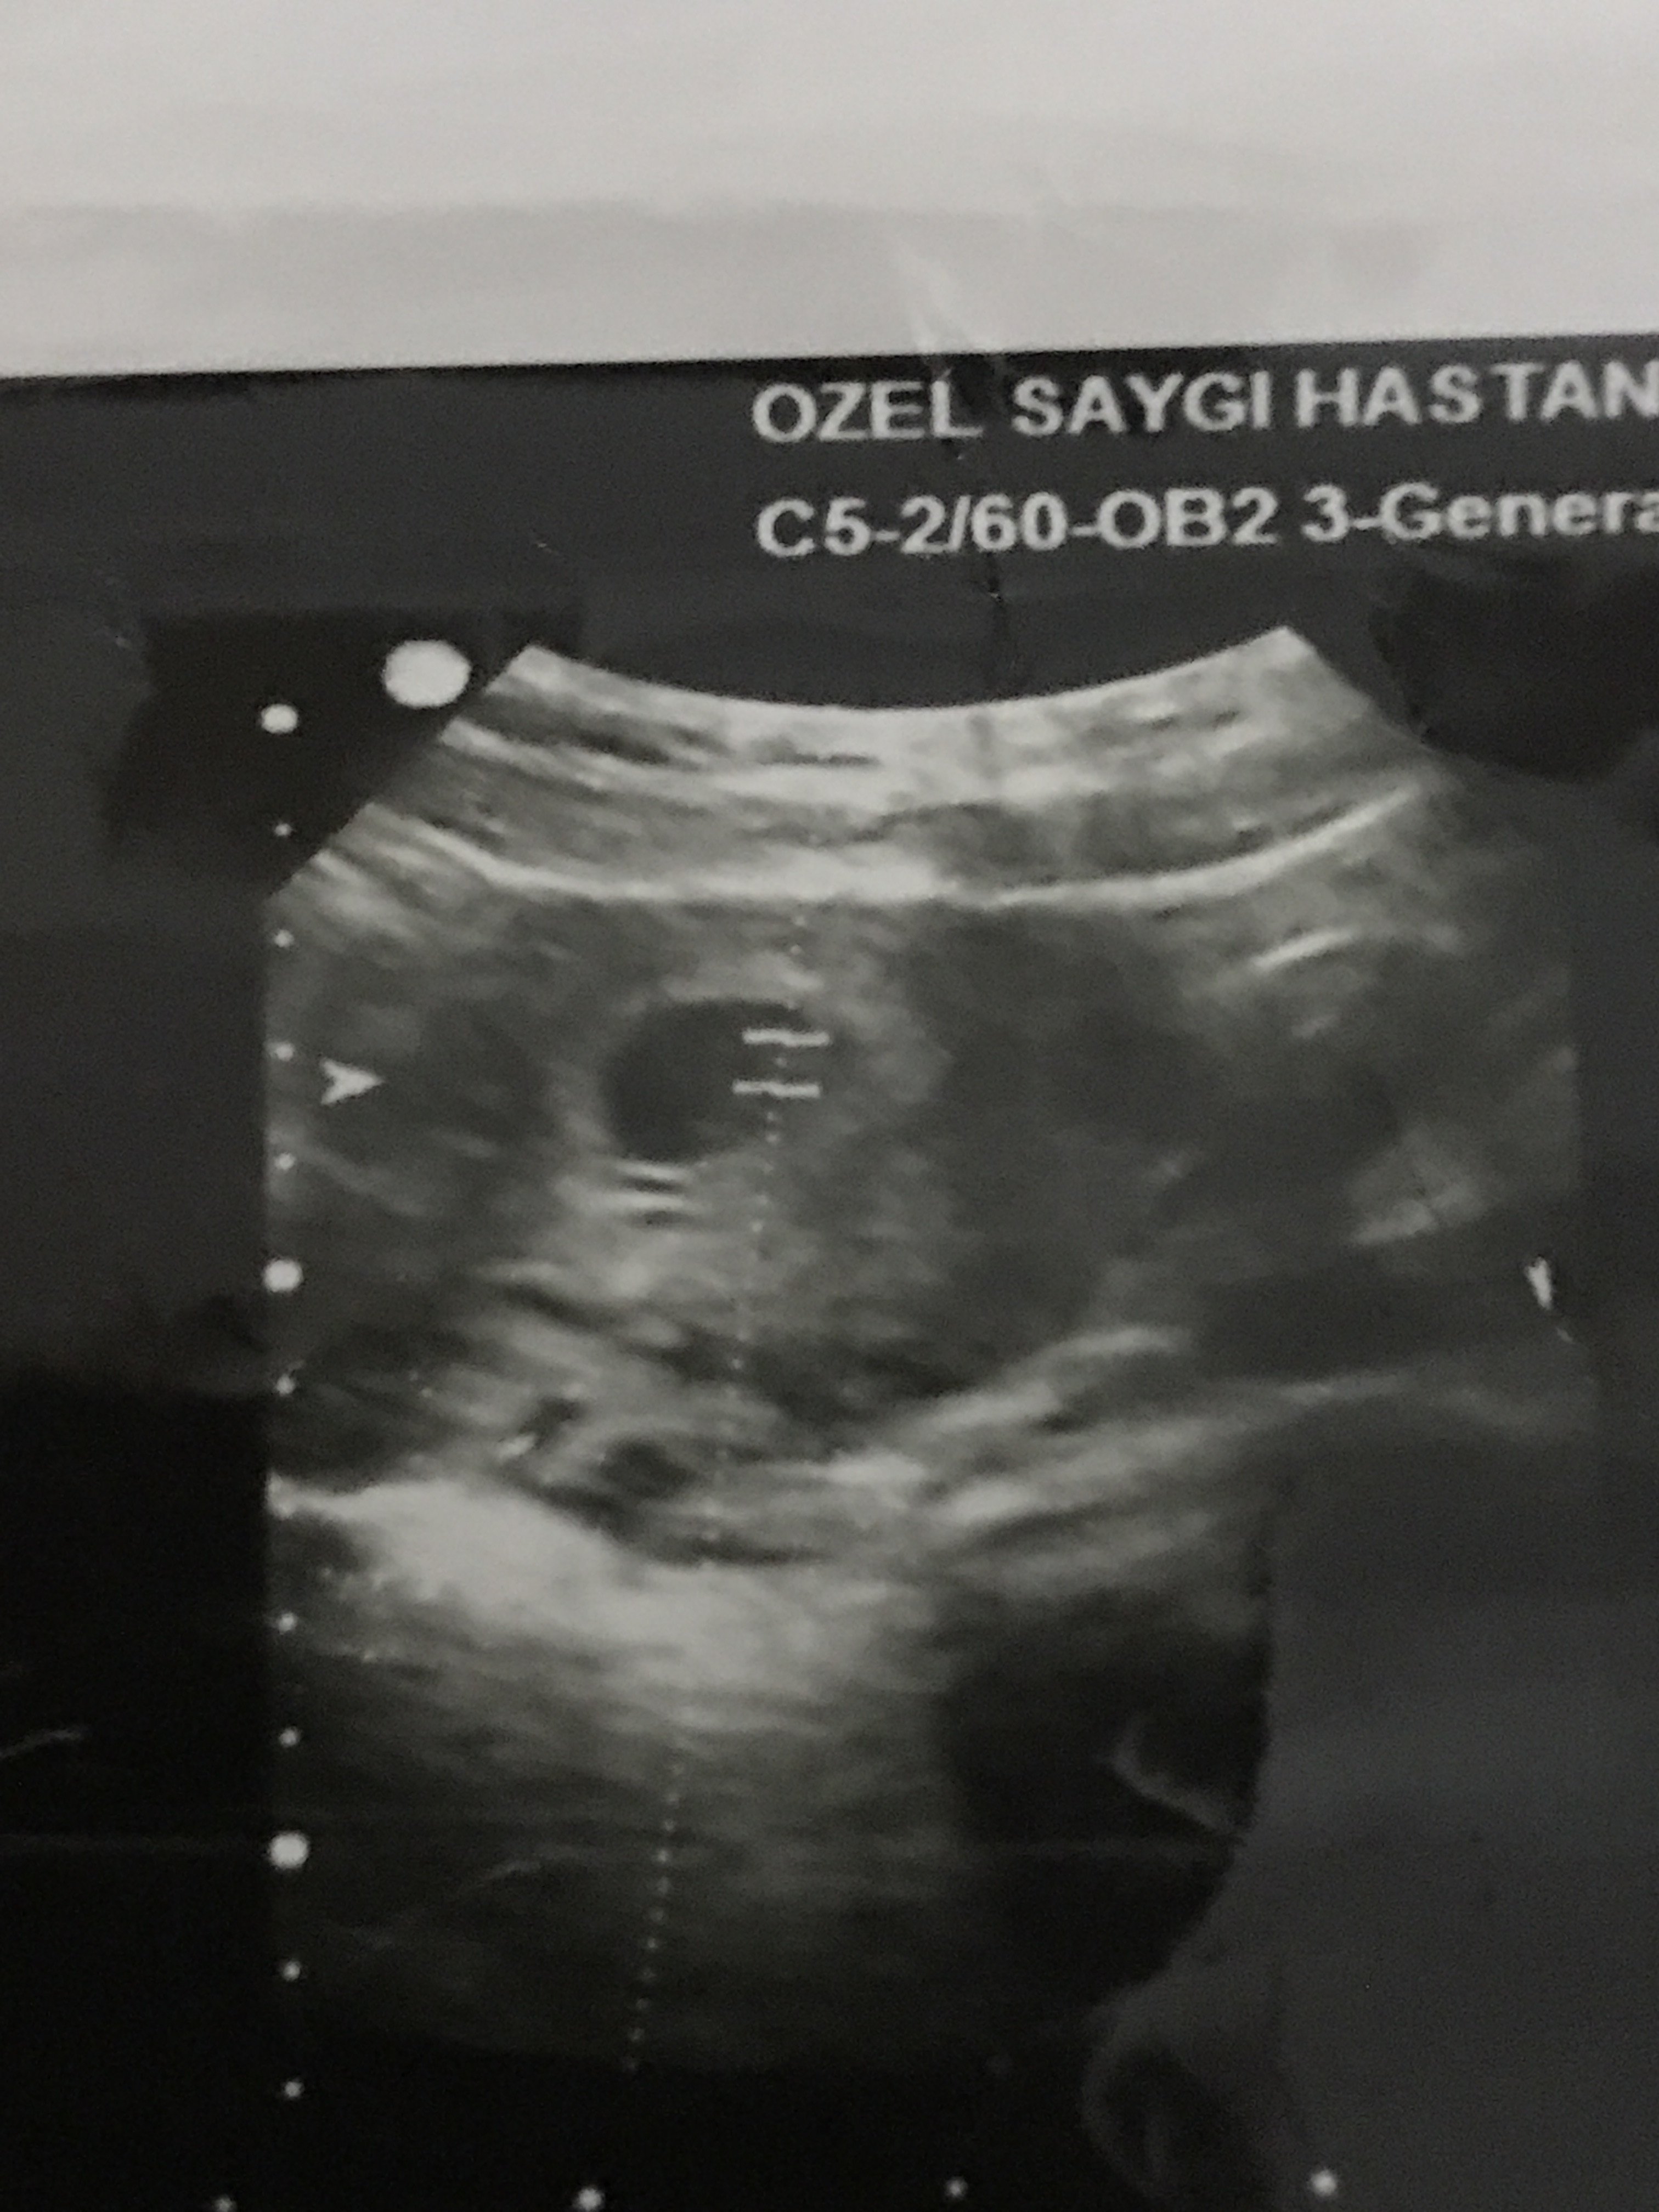

Merhaba .Bunlarda 6+4 günlük usg fotolarım.Ramzi teorisine göre de yorum yapabilir misiniz

Selamlar, bu yuvarlak kese olan bölümü yakın atar mısınız tam anlamı ile yorum yapamıyoruz görmediğimiz için